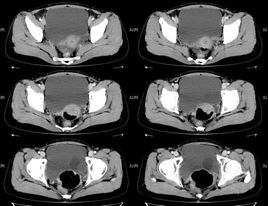

輸尿管囊腫又稱輸尿管疝或輸尿管口膨出,是由于先天性輸尿管口狹窄所致的膀胱壁內段輸尿管囊性擴張所致。輸尿管囊腫分為兩型:①單純型輸尿管囊腫:即膀胱內型輸尿管囊腫,輸尿管囊腫完全位于膀胱內,可以是單一輸尿管的輸尿管囊腫,無上尿路重復畸形,亦可并發于完全性重腎、雙輸尿管的,而極少是下腎之輸尿管。②異位型輸尿管囊腫:輸尿管壁內段的先天性擴張,并有輸尿管異位開口,輸尿管囊腫的一部分位于膀胱頸部后尿道,其開口可位于膀胱內、膀胱頸或尿道內,多伴有腎、輸尿管重復畸形,且囊腫多起源于上腎之輸尿管。